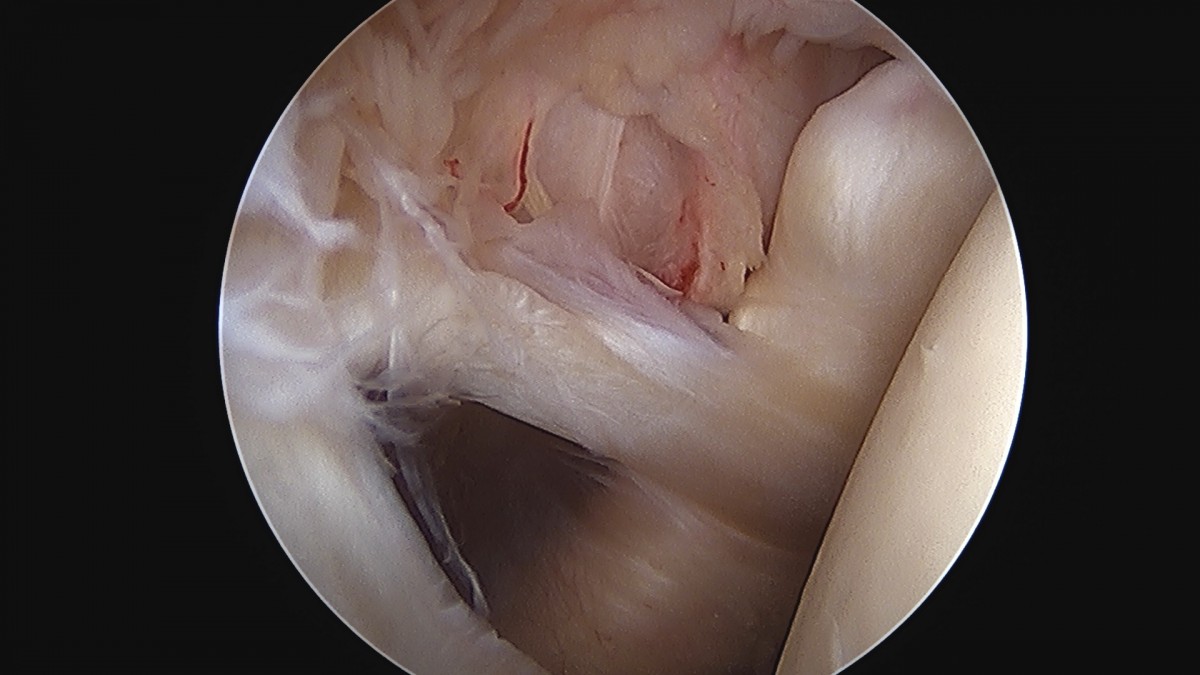

정지영원장님 어깨 회전근개 봉합술 임채O 환자

dae765e4d9ac96aee867c9d6292d8784_1758009113_696.jpg